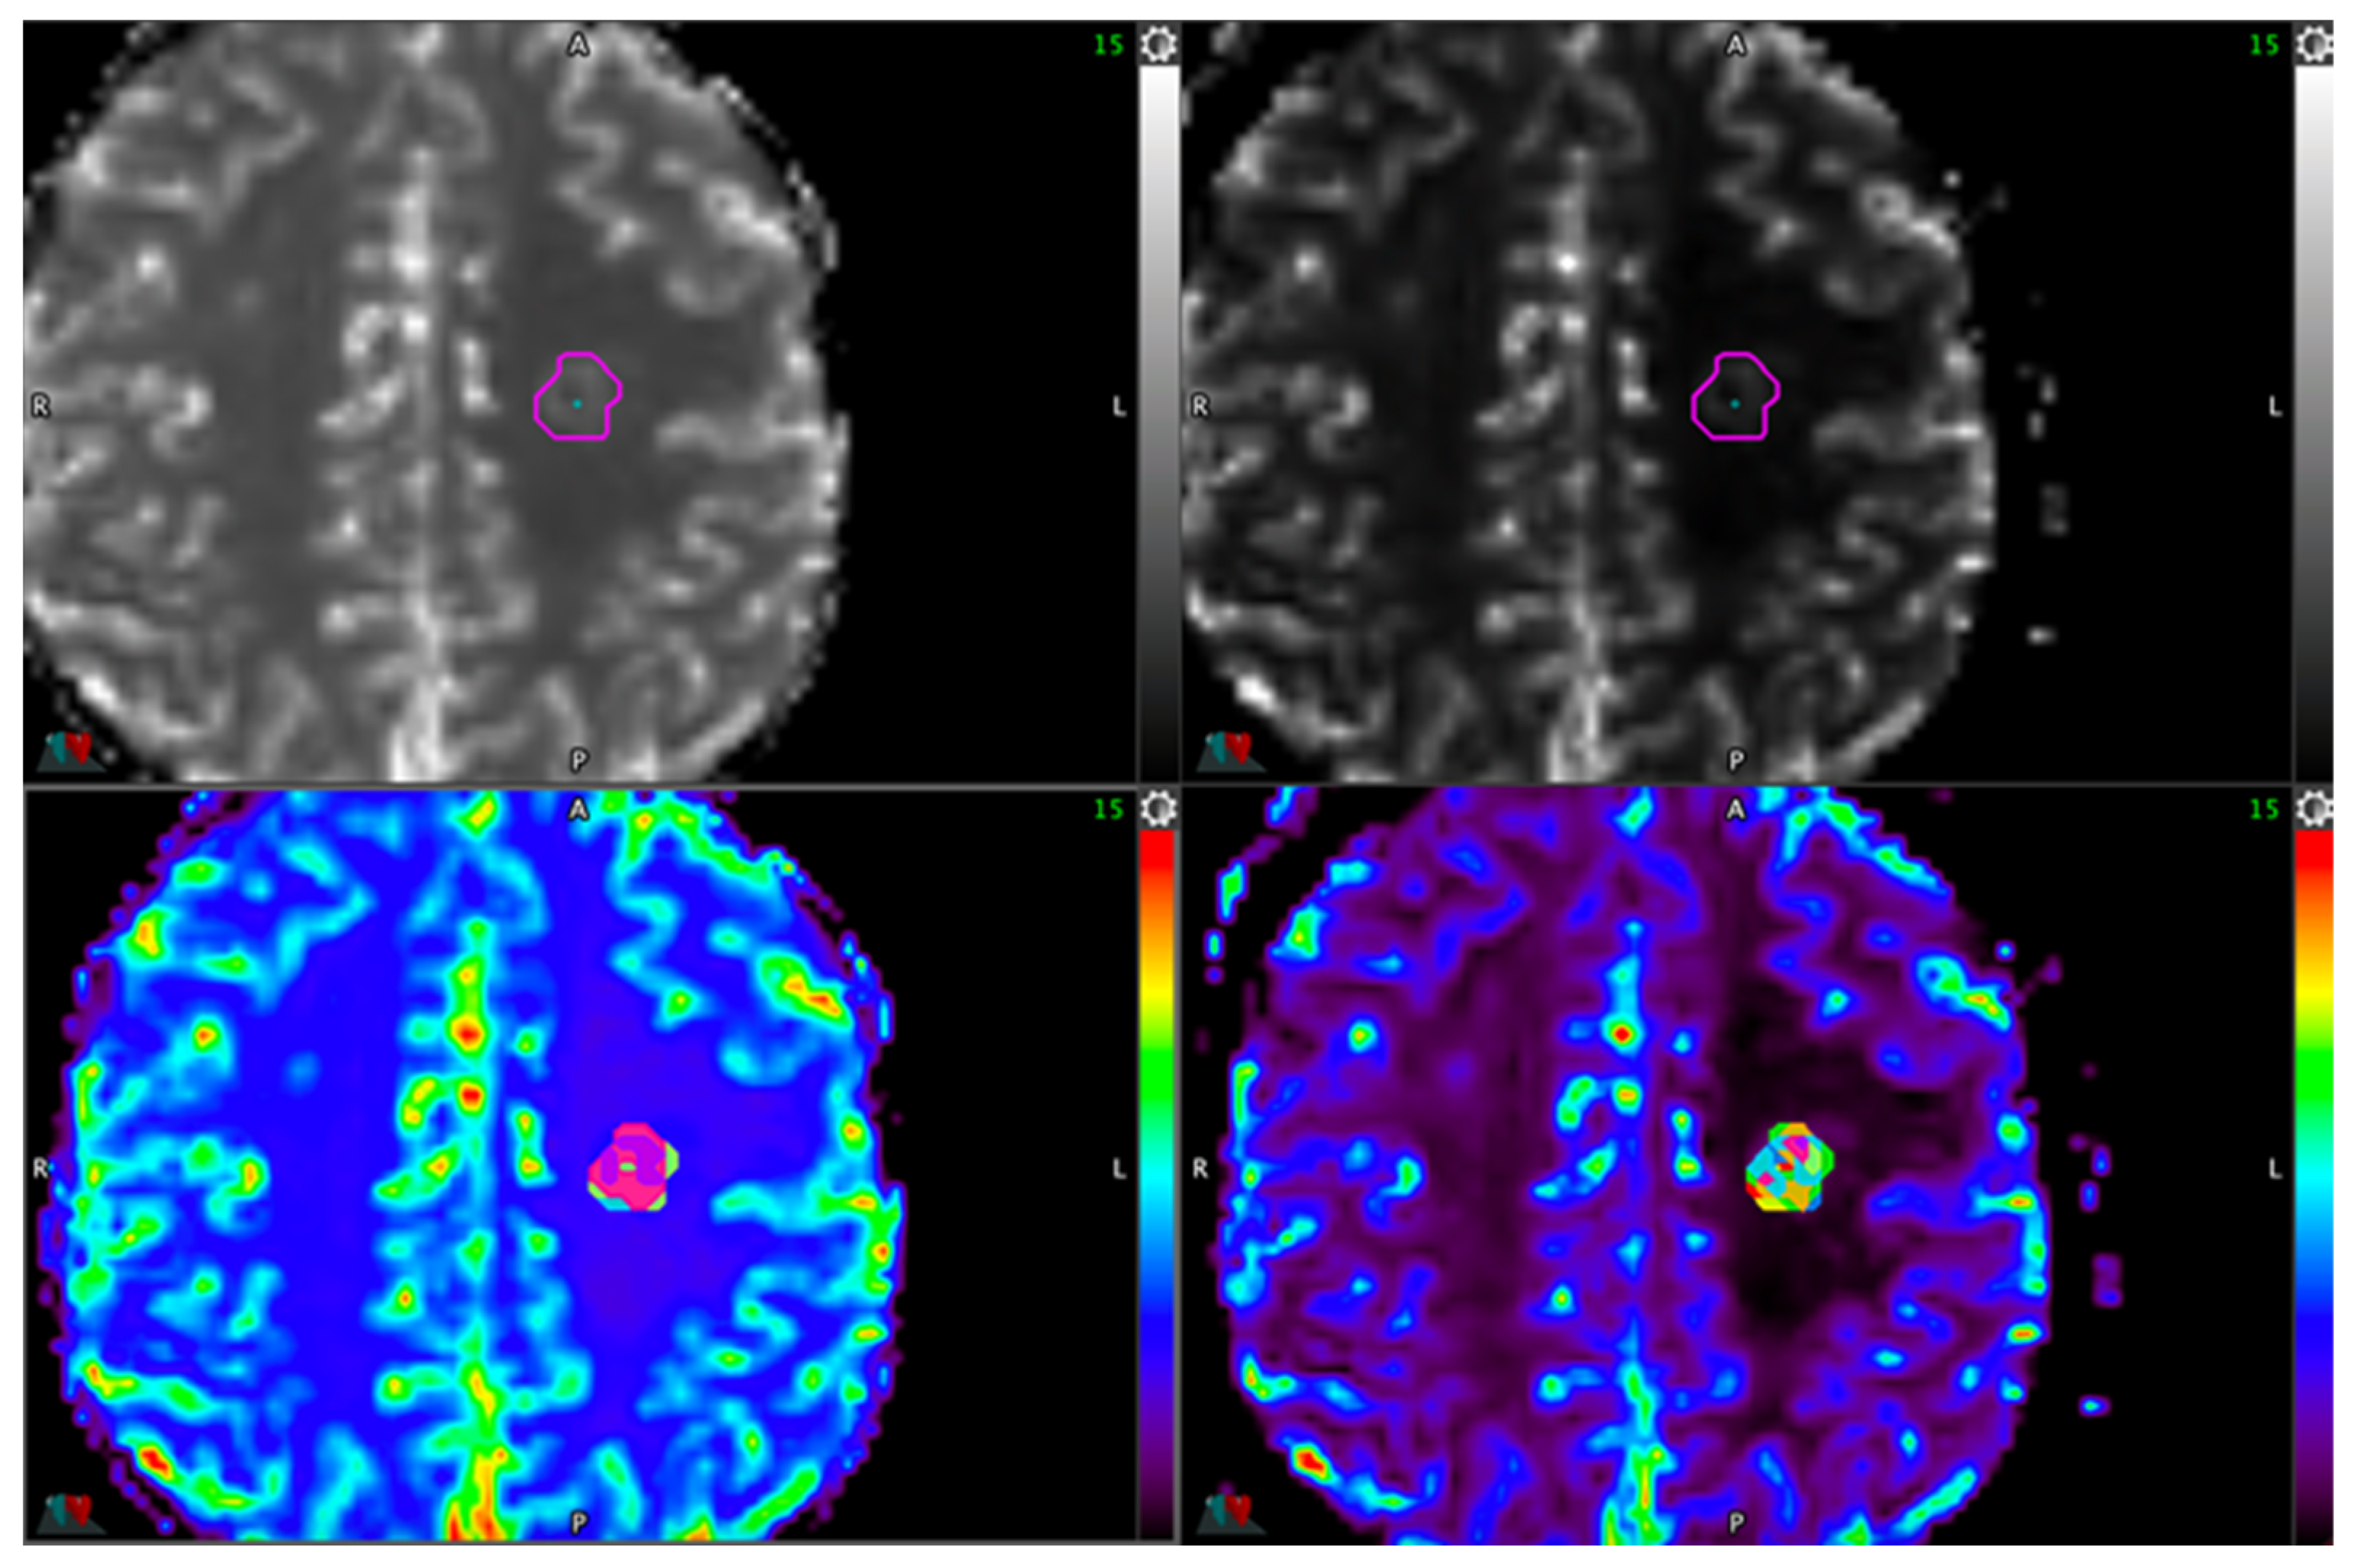

2.3. Processing of Cerebral Perfusion Maps

2.4. Lesion ROI Definition Delineation

2.4.1. Reference Method

2.4.2. Automatic Thresholding